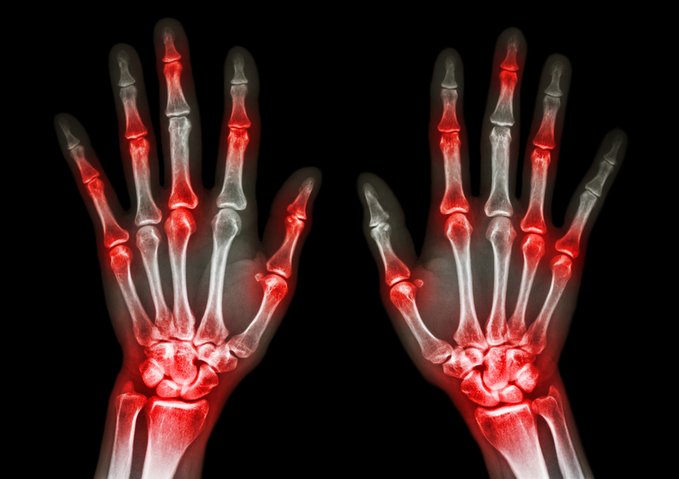

Avances en el tratamiento de la artritis psoriásica en adultos

Esta revisión describe las herramientas de evaluación y las medidas de resultado utilizadas en la evaluación de los pacientes con artritis psoriásica. Resume el enfoque de la terapia, incluidas las intervenciones no medicinales como la educación, los cambios en el estilo de vida, la fisioterapia y la terapia ocupacional. Se discute la evidencia sobre los tratamientos farmacológicos, incluidos los fármacos utilizados para el alivio sintomático, como los antiinflamatorios no esteroideos, y los utilizados para controlar el proceso de la enfermedad. BMJ   21 de noviembre de 2024